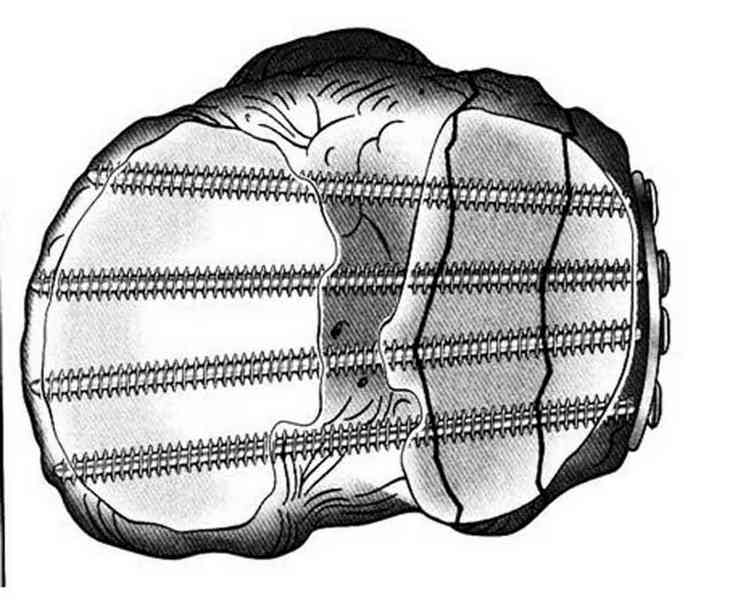

Основная задача в лечении околосуставных переломов является создание солидного базиса в субхондральной зоне. Пластина подпорка (Butress) или субхондральные перкутанные шурупы в виде плота (Raft) для ранних движении.

По этому если фрагмент большой есть необходимость репозиции дистального угла и фиксация пластинкой против соскальзывания ANTIGLIDING PLATE. Если перелом фрагментарный? то очень помогают описанные субхондральные шурупы RAFT, но

чтобы сохранить высоту суставной площадки шурупы одним концом должны опираться на пластинку а другим - на кортекс по внутренней стороне. Идеально сочетание ANTIGLIDING BUTRESS PLATE + RAFT SCREWS.

Все названные пластины не пригодны для фиксации мельких фрагментов. Сейчась многие компании имеют периартикулярные пластины достаточной длины с возможностью установки в мульти аксиальном направлении более тонкими шурупами вместо 3.5мм. Шурупы 2.7 мм не раскалывая позволяет удержать фрагменты в дистальном сегменте.

Пластина от DePuy отвечает всем требованиям, но могут быть и другие варианты. Репозицию закончивается костной пластикой или заполнением синтетическими заменителями иначе поведет в варус.